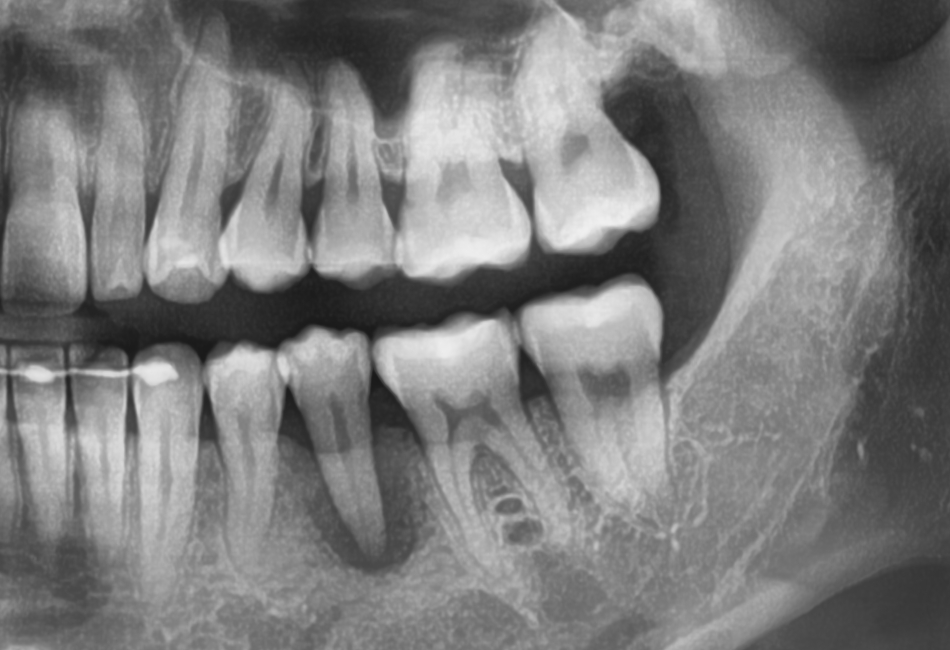

하악 좌측 제2소구치에서 관찰되는 광범위한 lesion.. 살짝 정출까지 돼 보인다.

CC. 왼쪽 아래 1년 전부터 아팠어요.

이번 주 일기의 메인이벤트는 이 케이스 이야기다. 외국에서 지내시느라 치료비가 비싸 치료를 못 받고 이제야 치과에 오셨단다. 많이 흔들릴 것 같아 흔들리지는 않냐고 여쭤보니 흔들리기도 하신단다. 체어를 눕히고 직접 동요도를 보니 이건 빼박 발친데 아.. 왠지 욕심이 났다. 근관치료는 과연 어디까지 가능한 걸까? 분명 저런 치아 살려낸 케이스를 봤단 말이지. 환자분께 이거 발치해야 된다고, 어딜 가도 다 발치하자고 할 거라고. 그랬더니 담담하시다. 근데 신경치료 원하시면 하다가 도중에 발치될 수도 있다고 말씀드리니 다른 치과에서 발치 이야기 듣고 왔다고 어차피 발치할 거 괜찮다고 하셔서 본인도 신경치료받아보고 싶어서 왔다기에 발치 고지 빡세게 하고 싸인도 받고 일단 A/O 진행했다. 20대 여환. 7월 중순 이후에 다시 출국하신다는데, 내년 3월에 돌아오시면 임플란트 하실 생각도 있다고 하셨다.

아무튼 그런데 치료 내내 치아가 정말 너무 많이 휘청거려가지고 '이거 안되겠다, 고정을 해야겠다' 싶어서 별생각 없이 당연스럽게 협설측 embrasure에 산부식 하고 flowable resin으로 스프린트를 해놨는데... 그게 수가가 있다는 생각 자체를 못하고 그냥 해버린~ 것이었던~ 것이었다😱. 고지를 안 하고 해서 그 부분 진료비를 못 받았는데 대표원장님 뒷목 잡으시는 거 아닌가 모르겠다. 이 진료는 거의 정말로 자원봉사가 되어버렸다. 스플린트 수가도 진짜 무시 못 한다.